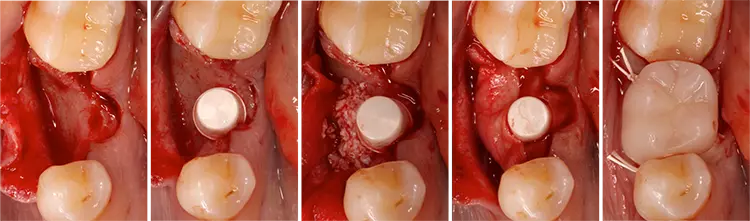

Die Implantate wurden im üblichen chirurgischen Vorgehen inseriert und sofort mit einem Provisorium aus Polymethylmethacrylat (CAD-Temp, VITA) versorgt, wobei die Provisorien außer Okklusion geschliffen wurden und darauf geachtet wurde, dass approximal nur sehr schwache Kontakte bestanden (Abb. 3a bis e). Die definitive prothetische Versorgung erfolgte im Unterkiefer nach frühestens 2 Monaten, im Oberkiefer nach frühestens 4 Monaten. Die Restaurationen wurden aus verblendetem Zirkonoxid hergestellt (VITA YZ HT / VITA VM 9, VITA).

Bei Knochendefekten ist eine Augmentation erforderlich. In der klinischen Studie „FR/ZH“ wurden in 11 Fällen kleinere simultane Augmentationen durchgeführt (vergl. Abb. 3). Die Augmentationen dürfen aufgrund der ermittelten Sondiertiefen und Röntgenbefunde als erfolgreich angesehen werden.

Vergleichbare Resultate lieferte die klinische Studie mit Fairwhite-Implantaten [29]. In jedem Fall muss der vom Hersteller vorgegebene Mindestwert für das Drehmoment bei der Implantatinsertion erreicht werden. Für die simultane Augmentation größerer Defekte liegen bisher nur Daten aus unserer Hundestudie vor [7].

Es wurden Bone-Level-Prototypen-Implantate auf der Basis des ceramic.implant verwendet. Nach deren Implantation wurde die bukkale Knochenwand entfernt. Die Knochendefekte wurden mit bovinem Knochenersatzmaterial (Bio-Oss, Geistlich Pharma, Wolhusen, Schweiz) verschiedener Darreichungsformen gefüllt, mit einer Kollagenmembran (Bio-Gide, Geistlich Pharma) abgedeckt und mit der Mukosa verschlossen.

Es gab nach 3 Monaten keine signifikanten Unterschiede zwischen den einzelnen Gruppen in Bezug auf den neugebildeten Knochen, das Knochenersatzmaterial und das nicht-mineralisierte Gewebe innerhalb des gesetzten Defektes. Augmentationsmaterial in Granulatform ? abgedeckt mit einer Kollagenmembran – hat für Zirkonoxidimplantate die besten Resultate im Hinblick auf den Erhalt der Knochenkontur geliefert. Die Resultate waren vergleichbar mit einer Kontrollgruppe, bei der Titanimplantate verwendet wurden.